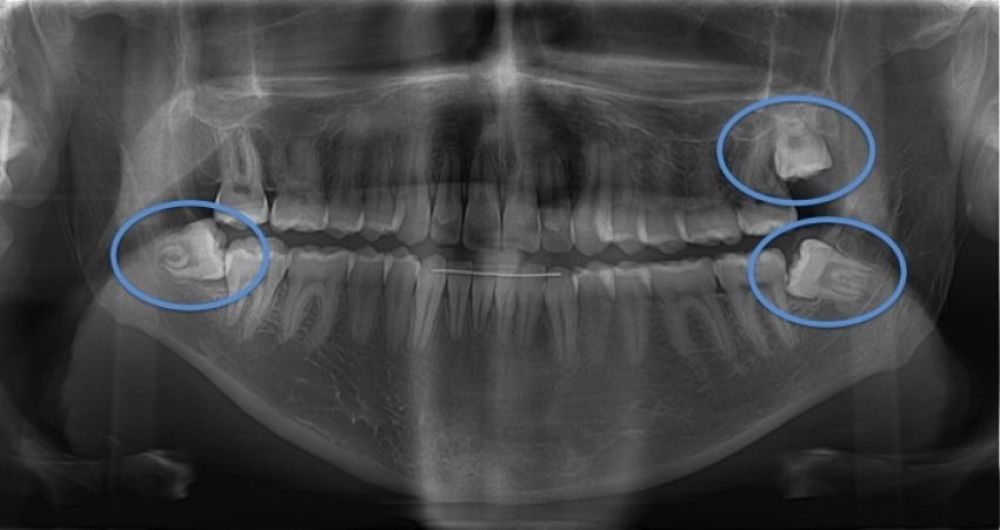

Extraer todos los cordales al mismo tiempo es una posibilidad cada vez más aceptada, tanto por la solicitud del paciente de perder el menor tiempo posible como por minimizar la necesidad de toma de medicación en múltiples ocasiones.

La indicación de las extracciones múltiples puede ser tomada por el profesional según la dificultad prevista o la posibilidad de complicaciones. Aunque se pueden realizar con anestesia local en el mismo acto quirúrgico, también es valorable la actitud del paciente ante este tipo de intervención, ya que si presenta mucha ansiedad, es preferible la sedación o la anestesia general para mejorar su confort, con lo que deberíamos hacer todo lo previsto de una sola vez.

En algunas ocasiones, si el paciente lo solicita o si ciertas circunstancias lo aconsejan, se pueden extraer de dos en dos bajo anestesia local llevando a cabo las extracciones de un lado de la cara en cada momento.